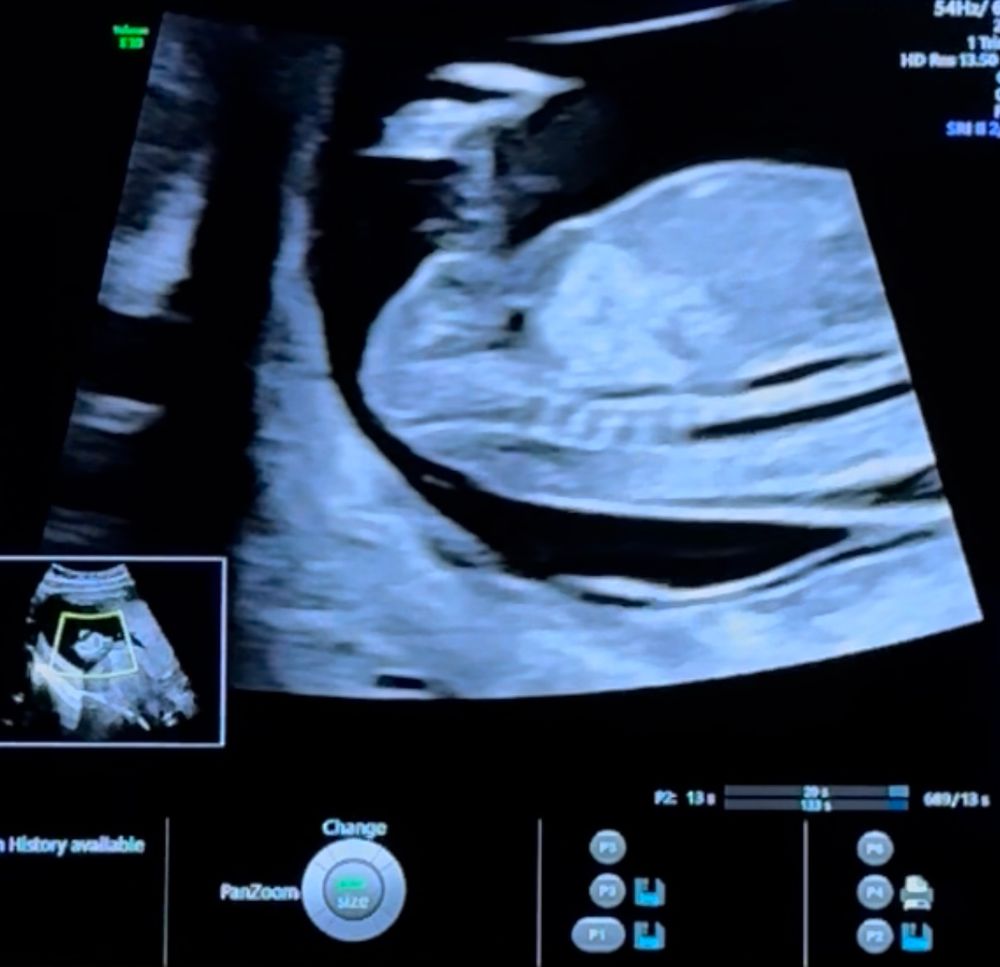

Пол ребенка в 12 недель (половой бугорок), мальчик или девочка?

за ножкой не видно бугорка(

Так не видно же.

Вроде как на девочку похоже, у мальчиков бугорок "крючёчком" вверх

Сбоку ножкой закрылся, а снизу на таком сроке не смотрят ☺️